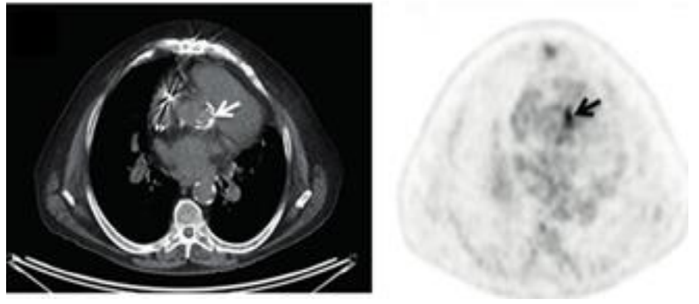

Homem de 70 anos, portador de prótese aórtica biológica há 4 anos, comparece à consulta com queixa de emagrecimento de

6kg em 2 meses, associado à sudorese noturna, febre não aferida e cansaço progressivo. Em uso apenas de ácido acetilsalicílico e

atorvastatina.

Ao exame: emagrecido, eupneico, hipocorado 2+/4+, desidratado. Dentes em mau estado de conservação. TAX: 39ºC, FC: 105 bpm, PA:

130x60 mmHg; ausência de linfonodomegalias ou alterações cutâneas; ausculta pulmonar sem ruídos adventícios; ritmo cardíaco regular

em 2 tempos, bulhas normofonéticas, sopro sistólico 3+/6+ em foco aórtico, com irradiação carotídea; espaço de Traube submaciço.

Membros inferiores sem edema.

Iniciada antibioticoterapia empírica após coleta de 3 pares hemoculturas de sítios diferentes, para aeróbios e anaeróbios. Ecocardiograma

transtorácico sem vegetações nas válvulas nativas, porém sem visualização adequada da válvula aórtica.

Após 3 dias, houve crescimento de Streptococcus mitis em 4 frascos de hemoculturas, de três sítios de coleta diferentes. Complementada a

investigação com uma tomografia computadorizada por emissão de pósitrons, que se encontra a seguir.

Homem de 70 anos, portador de prótese aórtica biológica há 4 anos, comparece à consulta com queixa de emagrecimento de

6kg em 2 meses, associado à sudorese noturna, febre não aferida e cansaço progressivo. Em uso apenas de ácido acetilsalicílico e

atorvastatina.

Ao exame: emagrecido, eupneico, hipocorado 2+/4+, desidratado. Dentes em mau estado de conservação. TAX: 39ºC, FC: 105 bpm, PA:

130x60 mmHg; ausência de linfonodomegalias ou alterações cutâneas; ausculta pulmonar sem ruídos adventícios; ritmo cardíaco regular

em 2 tempos, bulhas normofonéticas, sopro sistólico 3+/6+ em foco aórtico, com irradiação carotídea; espaço de Traube submaciço.

Membros inferiores sem edema.

Iniciada antibioticoterapia empírica após coleta de 3 pares hemoculturas de sítios diferentes, para aeróbios e anaeróbios. Ecocardiograma

transtorácico sem vegetações nas válvulas nativas, porém sem visualização adequada da válvula aórtica.

Após 3 dias, houve crescimento de Streptococcus mitis em 4 frascos de hemoculturas, de três sítios de coleta diferentes. Complementada a

investigação com uma tomografia computadorizada por emissão de pósitrons, que se encontra a seguir.